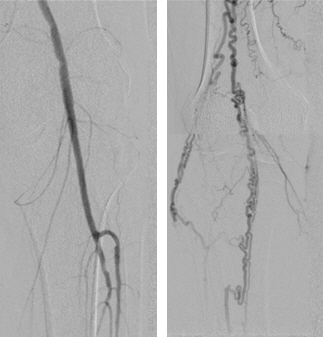

최근에는 인터벤션 영상의학 치료인 혈관성형술 사례가 늘고 있다. 국소마취 후 가느다란 카테터를 혈관 내로 삽입해 카테터에 달린 풍선으로 좁아진 혈관을 확장시키거나, 동맥이 다시 좁아지지 않도록 스텐트를 삽입해 문제 혈관을 정상화하는 방법이다. 최소침습 치료법이어서 환자 신체의 부담이 적고, 회복이 빠르기 때문에 선호도가 높다.

그러나 혈관성형술의 경우 이미 괴사가 상당히 진행된 상태로는 치료를 바로 시도하기 어려울 수 있다. 그래서 조기 진단이 중요한 것이다. 또한 말초혈관을 다루는 섬세한 시술이므로 경험이 많은 의료진과 상담 후 치료 계획을 세우는 것이 좋다. <스포츠조선 doctorkim@sportschsoun.com>